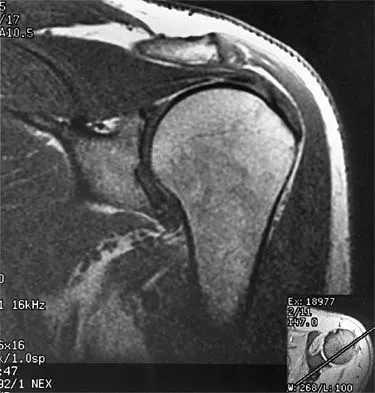

A patient has right shoulder pain. Figure 1a shows a gadolinium-enhanced transverse MRI scan at the level of the coracoid. Figure 1b shows an arthroscopic view of the anterior structures from a posterior portal. These images reveal which of the following findings?

The area shown in the arthroscopic view and MRI scan is referred to as a Buford complex and represents a normal labral variant. It consists of a thickened, cord-like middle glenohumeral ligament, a superior labral attachment of the middle glenohumeral ligament just anterior to the biceps tendon, and absence of the anterosuperior labrum. This combination of findings can be confusing and may simulate labral pathology. Mistaken repair of the lesion back to the glenoid rim can result in significant loss of external rotation. A Bankart lesion would be located at the inferior anterior glenoid rim. The subscapularis is seen anterior to the labrum. Normal variations that occur in the anterosuperior labrum can simulate pathology. Gusmer PB, Potter HG, Schatz JA, et al: Labral injuries: Accuracy of detection with unenhanced MR imaging of the shoulder. Radiology 1996;200:519-524. Griffin LY (ed): Orthopaedic Knowledge Update: Sports Medicine. Rosemont, IL, American Academy of Orthopaedic Surgeons, 1994, pp 47-63.

- Williams MM, Snyder SJ, Buford D Jr: The Buford complex: The "cord-like" middle glenohumeral ligament and absent anterosuperior labrum complex. A normal anatomic capsulolabral variant. Arthroscopy 1994;10:241-247.